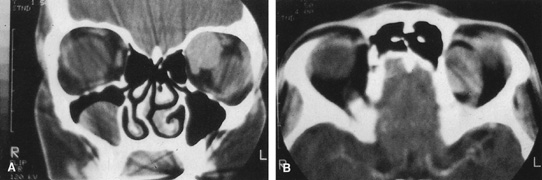

Valuable information about the nature and extent of an orbital pathologic process is provided by imaging studies such as computed tomography (CT) scan, magnetic resonance imaging (MRI), and orbital echography. Better spatial resolution, ready accessibility, and lower cost make CT the preferred choice for orbital imaging in most cases. Orbital fat provides a natural contrast between most adjacent orbital structures on CT scanning, and orbital bones are visualized well. Computed tomography is essential for evaluation of the orbital bones because they cannot be imaged with MRI. Direct coronal or sagittal images are important to identify the relationship of a lesion to the optic nerve so that the surgical approach can be planned to avoid traversing the optic nerve (Fig. 1).

Fig. 1. A. Axial CT scan demonstrating a large, well-encapsulated lesion in the orbital apex. Coronal (B) and sagittal (C) scans demonstrate that the mass lies inferior and medial to the optic nerve within the intraconal space. This information is useful in planning the surgical approach to the mass, which should avoid traversing the optic nerve.